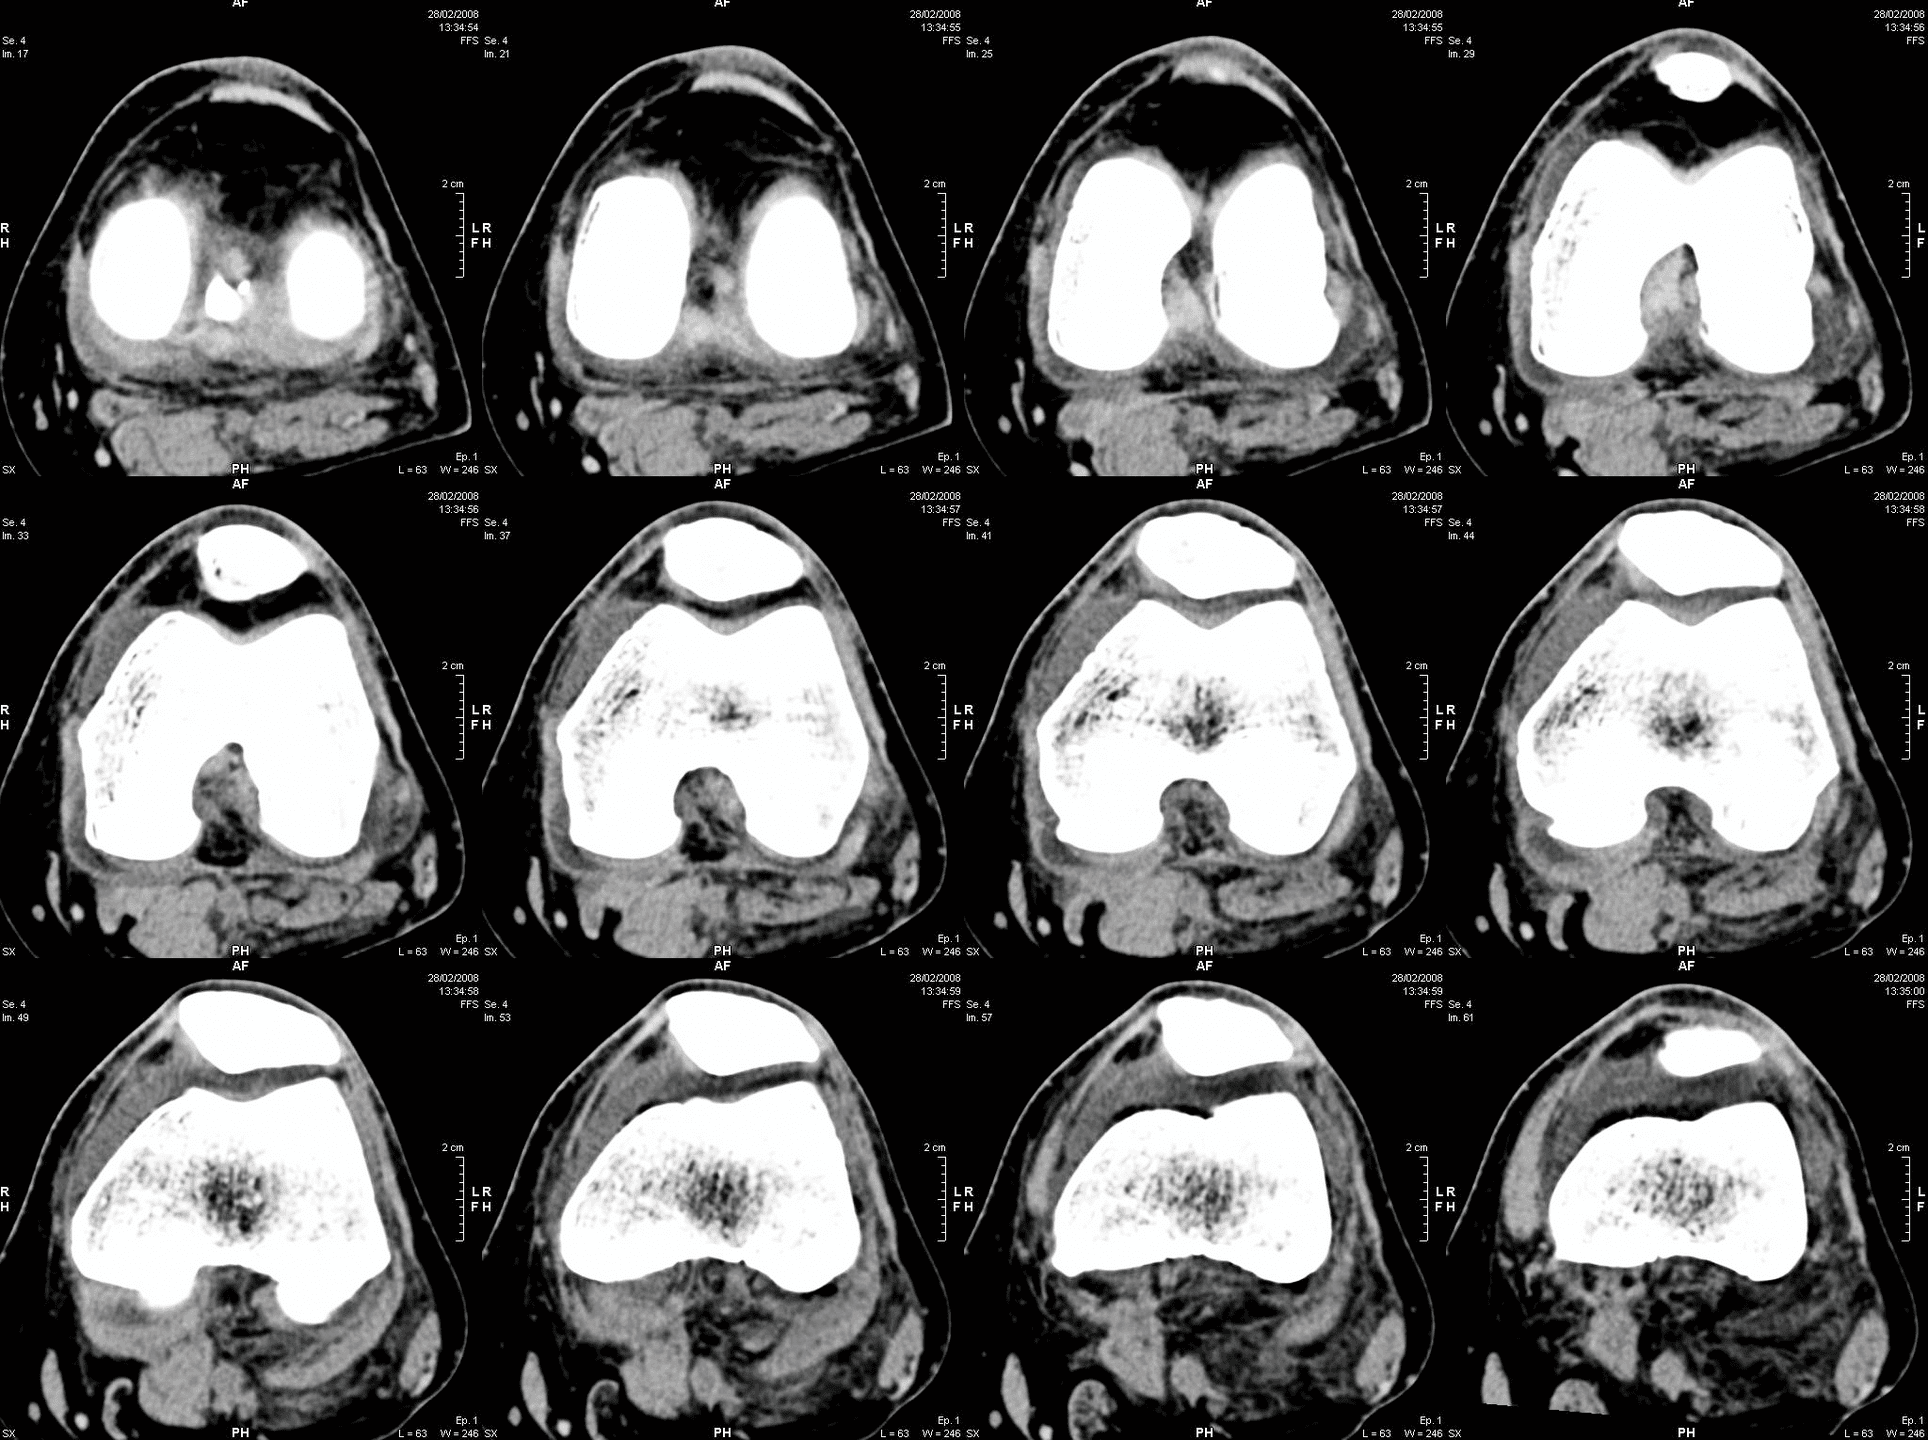

Maßgeschneiderter Operationsplan: vor der Operation wird eine Computertomographie (CT) Ihres Kniegelenks durchgeführt. Auf dieser Grundlage wird dann ein virtuelles 3D-Modell Ihrer individuellen Anatomie entwickelt. Das 3D-Modell ermöglicht es Ihrem Chirurgen, Details zu sehen, die normalerweise nicht mit Röntgenbildern allein zu sehen sind. Die von Mako bereitgestellten Informationen helfen Ihrem Chirurgen bei der Bestimmung der gewünschten Größe und Positionierung Ihres Implantats. Während der gesamten Operation stellt Mako SmartRobotics™ dem Chirurgen Daten in Echtzeit zur Verfügung, damit er die Bewegung und Spannung Ihres neuen Gelenks kontinuierlich beurteilen und Ihren Operationsplan bei Bedarf anpassen kann.

• CT-Scan des Gelenks – für detailliertere Informationen über die individuelle Knochenanatomie des Patienten bzw. der Patientin

• Virtuelles 3D-Modell des Gelenks: ermöglicht die genaue Planung für jeden Patienten bzw. jede Patientin

• Individueller präoperativer Plan: für Plananpassungen und funktionale Implantatpositionierung.